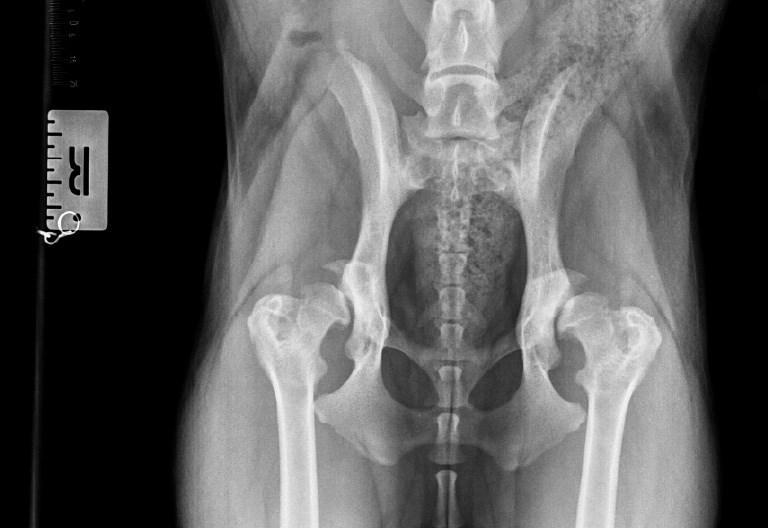

Example hip x-ray of a dog with hip dysplasia

Living with severe hip dysplasia is no picnic, for dogs or their owners. Dysplasia means the hip has developed abnormally. The soft tissues that connect and stabilise the joint become loose, and the ball and socket deform and sometimes drift apart. The dog experiences pain from repetitive strain injuries in the connecting tissues and microfractures from the bone and cartilage surfaces rubbing together and eroding – otherwise known as osteoarthritis.

Dogs suffering with the condition may limp, struggle to lie down or get up without groaning in discomfort, have difficulty climbing stairs or become reluctant to exercise. This can be deeply harmful for the physical and mental wellbeing of any dog, in particular athletic and heavier breeds.